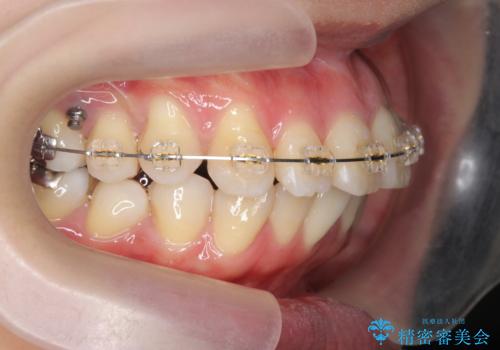

捻れた奥歯 突き出た前歯を治したい

- インビザライン +部分ワイヤー矯正

- 出っ歯に見える前歯、捻れてしまった小臼歯の改善を求めて来院されました。

マウスピースでは改善の難しい小臼歯のねじれをまず部分ワイヤー矯正で改善し、その後マウスピース矯正で前歯の突出感を改善します。

時間はかかりましたが、捻れ、かみ合わせ、前歯の角度の改善が達成され満足いただくことができました。